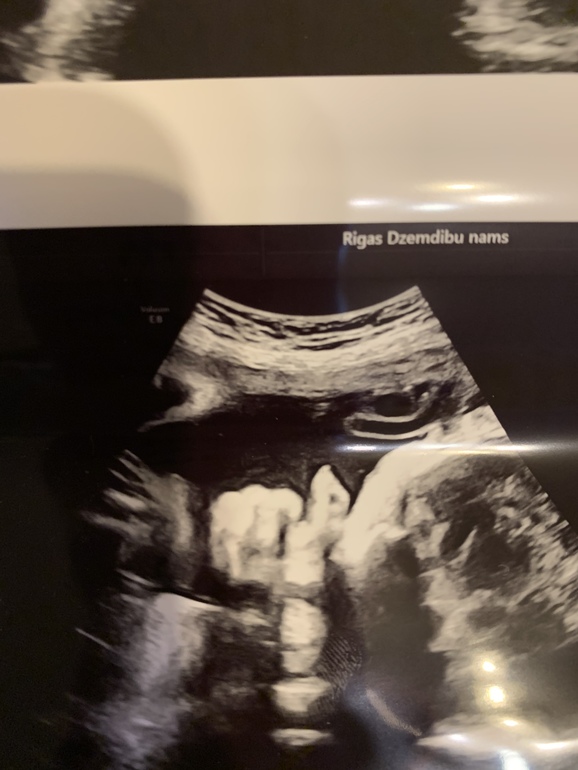

А тем временем идёт 31-я неделя. По плоду 32-я... Я больше не работаю. И понимаю, что лень напала))) Валяюсь дома, гуляю редко. Постоянно за рулем. А надо бы чаще бывать на свежем воздухе. Сегодня была на УЗИ. Плод, по всем параметрам соответствует 33 полным неделям! Опять ждать мне слонёнка))) Ну и фото нас на память. И просто и с узи.

Подтверждение пола)))